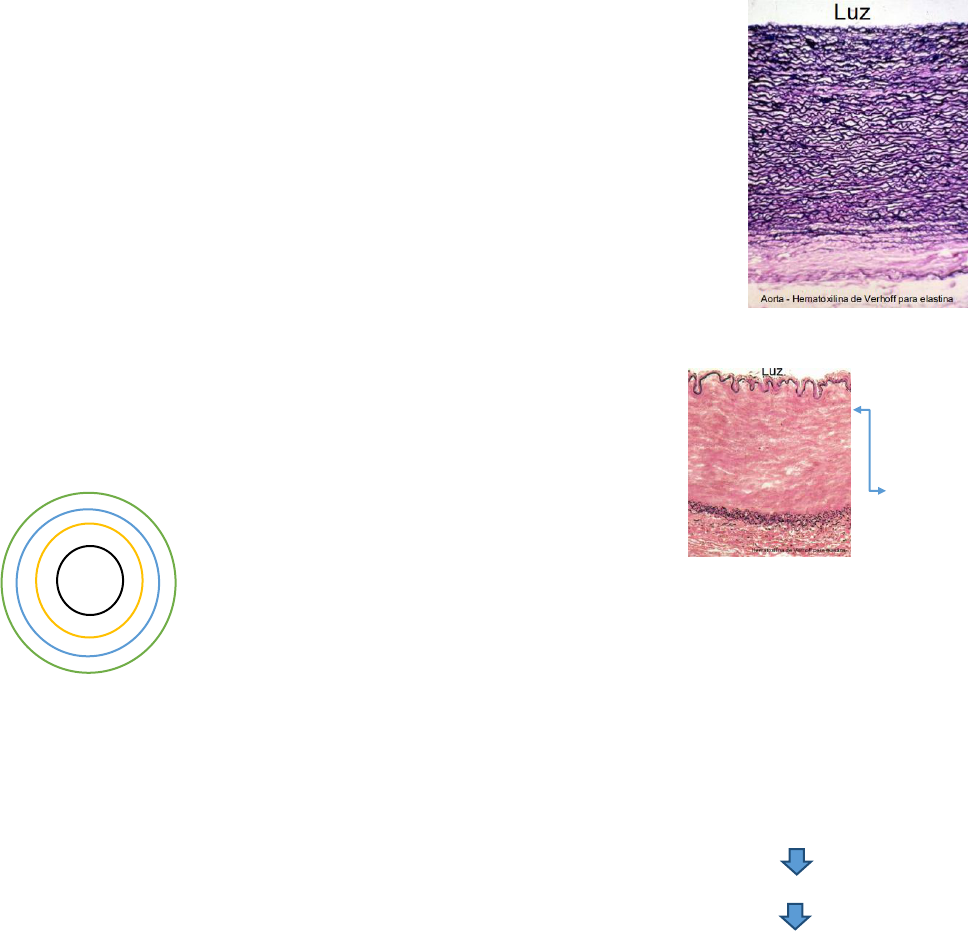

Estrutura dos vasos sanguíneos:

Túnica íntima:

- endotélio, mas lâmina basal: epitélio simples pavimentoso

- tecido conjuntivo frouxo: dá suporte estrutural e trófico.luz/

- lâmina elástica interna

Túnica média

- camadas de tecido muscular liso

- fibras elásticas

- fibras reticulares

- proteoglicanas e glicoproteínas

- lâmina elástica externa

Túnica adventícia

- tecido conjuntivo frouxo

- presença de nervos

- vasos da microcirculação: Vaso

Vasorum

Grandes Artérias = Artérias Elásticas

- Grande diâmetro e parede contendo grande quantidade de fibras elásticas